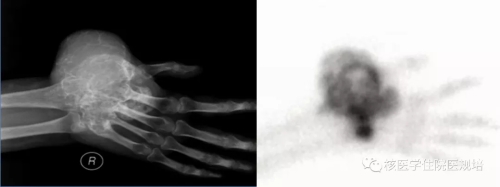

病史及检查目的: 患者63岁女性,4月余前无明显诱因出现持续性胸背部疼痛,沿肋间放射至胸部,左侧重,翻身及行走后加重,查体T4棘突压痛及叩痛(+)。行胸椎CT平扫+三维重建提示T4椎体变扁,后缘可见软组织密度影突向髓腔内,硬膜囊受压,考虑T4椎体病理性骨折可能。实验室检查:尿本周蛋白阴性;尿KAPPA轻链及LAMBDA轻链阴性;肿瘤标志物检测均为阴性。 为明确T4椎体病变性质、寻找骨转移原发灶行PET/CT检查(图2)。 图1.胸椎CT(骨窗) 图2. PET/CT图像 检查所见: T4椎体及附件区域见条状高度放射性浓聚(SUVmax:8.1),CT于相应区域可见溶骨性骨质破坏及软组织肿物影,向后累及附件并突入椎管内,椎体前缘骨皮质尚完整。左腋窝可见一FDG摄取增高淋巴结显影,考虑淋巴组织回流所致。扫描范围其余部位未见明显异常。 检查意见: T4椎体及附件骨质破坏呈葡萄糖代谢明显增高考虑恶性肿瘤可能,需鉴别原发灶不明的转移瘤、浆细胞瘤、骨巨细胞瘤、骨的嗜酸性肉芽肿及不典型淋巴瘤等,建议组织病理学检查。 手术及病理: 行胸椎椎管减压、椎弓根钉内固定术、病灶清除、椎体成形术,积水潭医院病理会诊:(胸4椎体)富含多核巨细胞病变,组织形态首先考虑骨巨细胞瘤。免疫组化:CK(-),Desmin(-),Ki67(10%-15%+),Vimentin(+),ActinSM(-),PGM-1(多核巨细胞+),KP-1(多核巨细胞+)。 病例相关知识: 骨巨细胞瘤(giant cell tumor of bone,GCT)为一种临床较为常见的骨原发性肿瘤,大部分为良性肿瘤,部分生长活跃,极少数一开始就是恶性。GCT具有丰富的血管组织并含有单核基质细胞和很多破骨细胞样的多核巨细胞,其中基质细胞决定肿瘤的性质。Jaffe等[1]首次定义GCT并根据基质细胞的异型性及有丝分裂活动进行病理分级,一般认为I级偏良性,Ⅲ级为恶性,介于两者之间的为Ⅱ级。目前WHO第四版骨与软组织肿瘤已将GCT定义为交界性肿瘤。与西方国家相比,国内GCT的发病率较高,约占所有原发骨肿瘤的20%[2]。女性发病率高于男性,多发生于青壮年,发病年龄多在20-40 岁之间,50岁以上的GCT约占9%-13%,青年人和儿童少见[3]。GCT多发生于骨骺融合后成熟的骨端[4],侵犯长骨多见,*常见于股骨下端、胫骨上端,约占50%以上,发生于非长管状骨如脊柱、骨盆、手骨、颌骨、颅骨等的GCT约占20%,但近年来也有报道GCT在脊柱的发病率增加。该病*常见的症状为肿瘤部位的疼痛与肿胀,且疼痛有活动后加重、休息后缓解的特点,手术是治疗GCT的主要方法,目前亦有一些RankL拮抗剂用于术前药物治疗。 GCT的影像表现具有一定特异性,X线平片表现为骨端偏心性、囊性、膨胀性、溶骨性骨质破坏, 无明显硬化缘,骨包壳完整或部分缺如,部分肿瘤内可见骨性分隔,呈“皂泡样”改变(图3)。CT较X线具有较高的分辨率,能更加细致入微地观察骨质破坏情况,可观察到骨质破坏区内残留的骨嵴,与X线平片上“皂泡样”改变相对应,还可以能清晰地显示破坏区内部结构及软组织肿块及周边残留的骨壳。MRI检查能够清晰显示骨巨细胞瘤的大小、位置及形态,且对肿瘤附近的水肿状况进行清晰显示,在诊断病变范围上的价值较X线与CT检查更高。在MRI检查中,肿瘤的实质部分多呈T1WI与T2WI等信号,其内常可见多发混杂信号影,提示肿瘤内部常伴有坏死、囊变和出血。 图3. 骨巨细胞瘤的皂泡样改变(左:X线片,右:99mTc-MDP骨显像)(北京大学人民医院提供) 尽管骨肿瘤的*终诊断的确立需要临床、影像、病理三结合,即“CRP诊断”,但典型的影像表现对早期临床诊疗决策的建立十分重要。18F-FDG PET/CT全身大视野成像有助于发现肿瘤累及区域,通过发现多发病灶,首先可帮助检出转移瘤或血液系统肿瘤。然而,本病例PET/CT所见为脊柱单发病变,其鉴别诊断面临更多的挑战。由于病灶呈溶骨性骨质破坏并软组织肿物形成,椎体出现病理性骨折且软组织肿物压迫硬膜囊,同时肿瘤呈FDG高摄取,鉴于患者年龄偏大,应首先怀疑恶性病变。患者无肿瘤标志物升高且PET/CT无原发肿瘤病灶显示,不支持上皮源性肿瘤脊柱转移,但从发病机率应考虑有无原发灶隐匿的可能性;病变椎体前缘保留较完整,提示肿瘤侵袭性不强,不符合侵袭性淋巴瘤或一些高度恶性肉瘤的常见表现;单发浆细胞瘤多为溶骨性且可呈膨胀性改变,破坏区可见残留的骨壳和骨嵴,但一般FDG摄取程度相对较低;骨的嗜酸性肉芽肿属于朗格汉斯组织细胞增生症虽可累及脊柱并出现病理性骨折,其FDG摄取程度亦较高,但该病多见于年轻人群。回顾性分析该患者年龄虽然不属GCT好发人群,但亦可发病,而较高的FDG摄取和较温和的骨质破坏可符合GCT表现,然而由于椎体压缩性骨折使得CT对肿瘤形态和内部结构改变的观察不满意。若能获得典型的GCT CT表现,GCT诊断应该首先考虑(图4)。 图4.典型脊柱骨巨细胞瘤的PET/CT及MRI(北京大学人民医院提供) 对于原发性骨肿瘤,18F-FDG PET/CT的摄取与肿瘤成分密切相关,富含巨细胞的肿瘤(骨巨细胞瘤、未分化肉瘤、朗格汉斯组织细胞增生症等)多可见较高FDG摄取,甚至高于常见的恶性骨原发性肿瘤(骨肉瘤、软骨肉瘤、尤文肉瘤等),而良性肿瘤或者细胞成分稀疏的恶性肿瘤FDG摄取程度较低。 小结: 本病例并非典型的骨巨细胞瘤,通过此病例提出这一临床可能遇到的情况,希望为规培的小伙伴们提供脊柱病变的鉴别诊断思路。同时强调对于骨肿瘤的诊断一定是临床、影像、病理的综合分析,对常见的骨原发肿瘤相关知识应加以了解。 作者:中日友好医院核医学科 韩萍萍 郑玉民 参考文献: [1] Jaffe Hk, Lichtenstein L, Portis RB. Giant cell tumor of bone: Its pathologic appearance, grading, supposed variants and treatment. Arch Pathol, 1940, 30: 993. [2] Szendröi M. Giant-cell tumour of bone. J Bone Joint Surg Br, 2004, 86: 5-12. [3]Murphey MD, Nomikos GC, Flemming DJ, et al. From the archives of AFIP. Imaging of giant cell tumor and giant cell reparative granuloma of bone: radiologic-pathologic correlation. Radiographics, 2001, 21: 1283-1309. [4] 段承祥,王晨光,李健丁主编. 骨肿瘤影像学. 科学出版社, 2004年第一版。